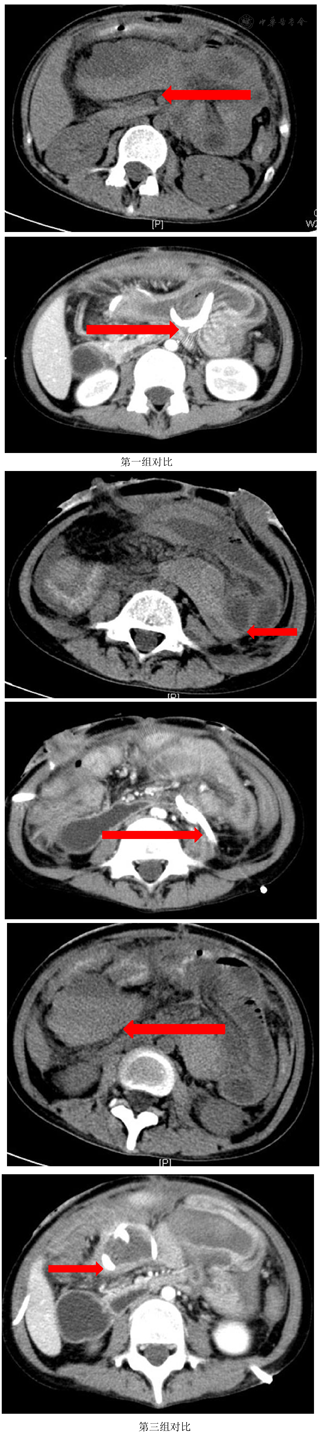

实验室检查:白细胞计数9.2×109/ L,中性粒细胞88.3%,血红蛋白56 g/L,降钙素原124 μg/L,白蛋白22.1 g/L,前白蛋白20 mg/L。消化道道造影提示,经肛门注入造影剂,可见只有直肠中下段显影良好其余结肠显示不清,广泛结肠及直肠炎,回盲部也受累(图1)。经外瘘口注入造影剂,见左盆腔不规则脓腔显影(图2)。骨密度检测提示骨质疏松。

2018年1月,患者左下腹再次破溃流出肠液,再次置入黎氏双套管冲洗引流。腹部CT提示:乙状结肠仍梗阻,肠壁增厚,回盲部炎症狭窄,直肠周围炎(图5,图6)。